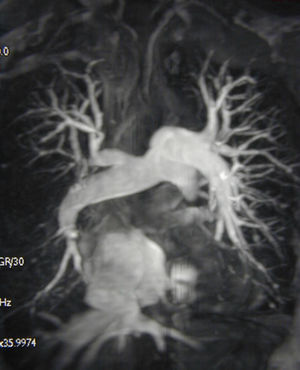

Magnetic resonance imaging angiogram demonstrating chronic thromboembolic pulmonary hypertension in an operable distribution, affecting the right middle and lower lobes as well as the left lower lobe. There is also evidence of tricuspid regurgitation with retrograde flow of contrast into the hepatic veins.